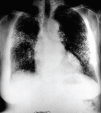

Fig. 1. Radiografía de tórax posteroanterior en inspiración: infiltrado intersticial de predominio micronodular difuso en ambos campos pulmonares.

Fig. 2. Radiografía de tórax en espiración y proyección posteroanterior en la que se aprecia infiltrado intersticial de carácter micronodular.